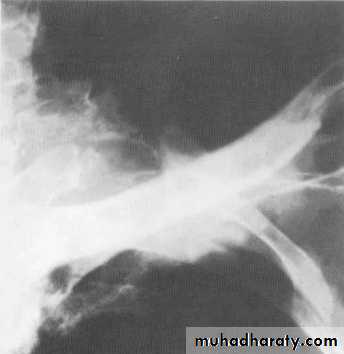

* Tramline: horizontal, parallel lines corresponding to (cylindrical ) thickened, dilated bronchi

* Bronchial wall thickening (best seen end-on) as honey comb appearance ( cystic ) .

Signet ring sign : focally thickened bronchial wall adjacent to pulmonary artery branch .